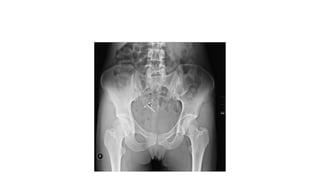

• Uterine perforation

• More commonly occurs when insertions are performed between 48 hours

and 6 weeks postpartum

• Conclusive diagnosis of perforation is usually made by a pelvic X-ray